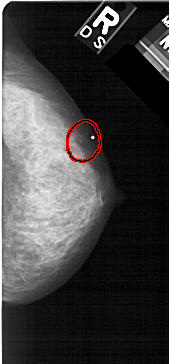

A_1472_1.LEFT_MLO

LEFT_MLO LINES 5371 PIXELS_PER_LINE 2506 BITS_PER_PIXEL 12 RESOLUTION 43.5 NON_OVERLAY

RIGHT_MLO LINES 5491 PIXELS_PER_LINE 2551 BITS_PER_PIXEL 12 RESOLUTION 43.5 OVERLAY

FILE: A_1472_1.RIGHT_MLO.OVERLAY

TOTAL_ABNORMALITIES 1

ABNORMALITY 1

LESION_TYPE CALCIFICATION TYPE PLEOMORPHIC DISTRIBUTION CLUSTERED

ASSESSMENT 4

SUBTLETY 4

PATHOLOGY BENIGN

TOTAL_OUTLINES 1

BOUNDARY